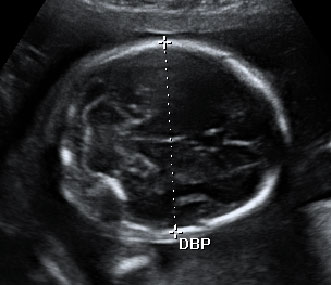

Esta ecografía 4D de la semana 20 de embarazo muestra que los bebés prácticamente empiezan a chuparse el dedo dentro del útero materno. El feto se acerca el dedo pulgar a la boca y en las imágenes finales la abre, muy probablemente para chupárselo.